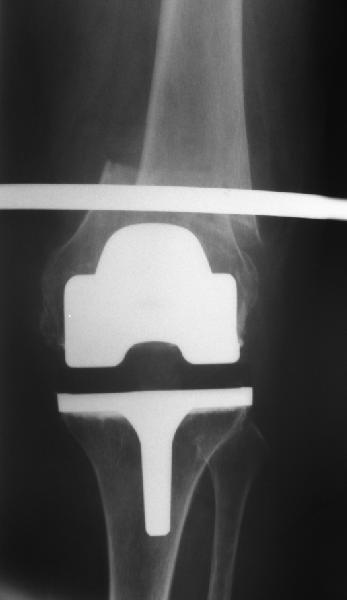

То, что планируется - наиболее распространенный подход. Еще менее инвазивный вариант - закрытый антеградный интрамедуллярный остесинтез. Мы используем гвозди, которые выпускаются предприятием ЦИТО, т.е. недорогие. Там в дистальное отверстие можно ввести 3 винта (2 снаружи и один навстречу), еще и угловая стабильность получается.